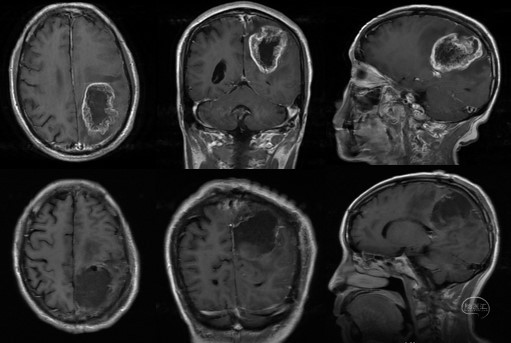

(二)左侧功能区巨大胶质母细胞瘤全切一例

患者,男,73岁,右侧肢体无力1月余,查体右侧肢体肌力I级。

术前磁共振检查提示左侧功能区巨大胶质母细胞瘤。手术全切肿瘤,术后复查证实肿瘤全切,术区无明显渗血、水肿。

患者术后肌力立即恢复至V级,无神经功能障碍。患者依从性差,拒绝进一步放化疗,失访。